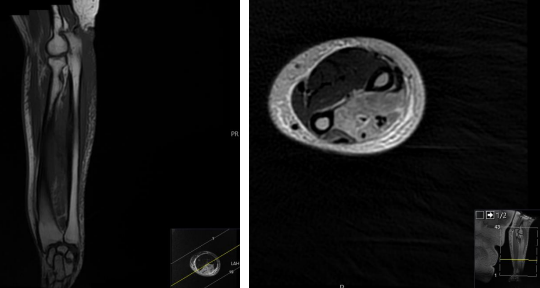

MRI Forearm Lt (non-contrast) report:

The muscles within the posterior compartment of the forearm, including the extensor muscles, are diffusely enlarged and demonstrate increased signal intensity on T2-weighted sequences with anterior bowing of the deep fascia. No obvious internal collections to suggest abscess formation.

Note is also made of extensive subcutaneous oedema. The oedema extends from the wrist to the elbow, involving the soft tissues and the muscles of the forearm. There is no evidence of any underlying bony or joint abnormalities.

The flexor muscles within the anterior compartment of the forearm are within normal limits with no evidence of injury or oedema.

The tendons and ligaments are intact, with no evidence of tearing or avulsion.

Photo 1 : Axial STIR Left Forearm          Photo 2 : Cor STIR  Left Forearm

Photo 3: Cor T1 Left Forearm                  Photo 4: Axial T2 PR Left Forearm

Conclusion of MRI:

Diffuse thickening an oedema change involving the muscles of the posterior compartment and the subcutaneous oedema. Given the patient's history of antiphospholipid syndrome and recent trauma followed by severe pain, the MRI findings could be in keeping with suspected compartment syndrome, this needs urgent surgical review.